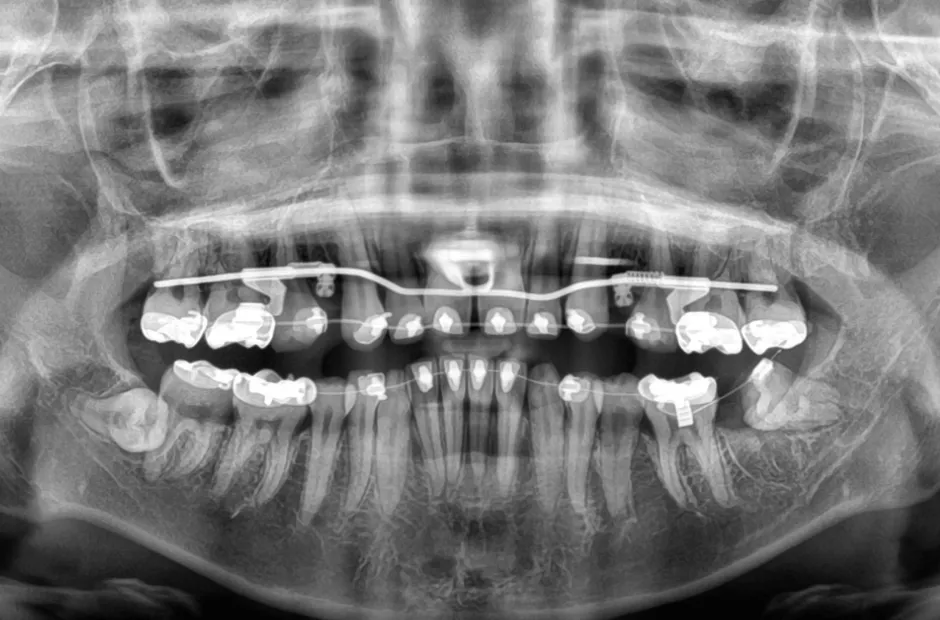

叢生

| 診断名・主訴 | 叢生 |

|---|---|

| 年齢・性別 | 43歳・女性 |

| 治療期間・回数 | 2年7か月 27回 |

| 治療に用いた主な装置 | 舌側矯正 |

| 抜歯部位 | 両顎4,4 |

| 治療費 | 100万円(税抜) |

| リスク・副作用 | 装置による違和感・疼痛・歯肉退縮・歯根吸収・虫歯のリスクなど |

治療中